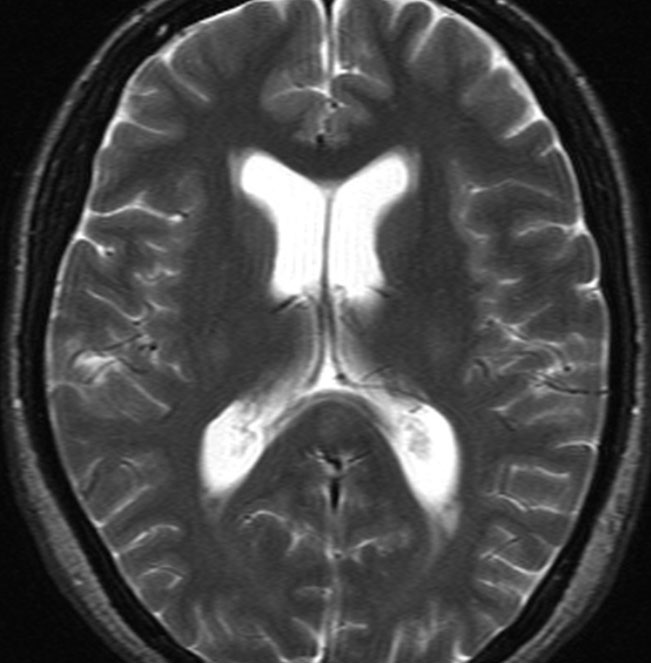

上矢状洞髄膜腫 superior sagittal sinus meningioma

上矢状洞を埋め尽くすように増大して,頭蓋骨浸潤が著しい髄膜腫ですが,ごく軽度の右足脱力以外に何の症状もありません。上矢状洞はゆっくり閉塞すれば,このような頭頂部から後頭部にわたる広範閉塞でも,静脈還流に障害がない場合が多いといえます。大脳の前半部の血流は前頭葉表面の皮質静脈から海綿静脈洞に側副路を形成しています。頭蓋内圧亢進所見もなく,これらはこの髄膜腫がゆっくり増大したということを示唆しています。

手術直後の画像です。全部いっぺんに摘出するのは無理なので,まず前から80%くらいの腫瘍を摘出しました。肥厚した骨はチタンプレートで置き換えてあります。後頭部の上矢状洞内と大脳鎌に少し残りましたが,この6ヶ月後に2回目の開頭術をして全摘出しました。結果的にこの例では,上矢状洞を冠状縫合のあたりから,静脈洞交会まで壁ごと全部摘出しましたが,脳浮腫も何も生じませんでした。腫瘍の両側にある皮質静脈 cortical veinsを損傷しないことが肝要です。

右の病理像は,頭蓋骨浸潤している部分 ですが,骨破壊は良性髄膜腫に特徴的な骨内浸潤像です。この骨浸潤像は悪性像とはいえません。MIB-1は高いところで8%、低いところで3%程度です。